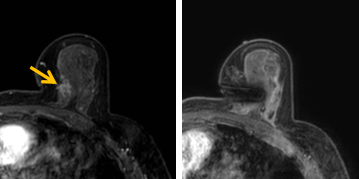

患者李女士磁共振檢查發(fā)現(xiàn)右乳內(nèi)側(cè)高度可疑病變,病變小摸不到,超聲和X線攝影(鉬靶)都看不到,怎么辦?要想明確病變性質(zhì),必須進(jìn)行磁共振引導(dǎo)下精準(zhǔn)足量的活檢,但是這種技術(shù)操作難度大、軟硬件要求高。

經(jīng)過(guò)仔細(xì)查體并分析所有影像資料,陳寶瑩發(fā)現(xiàn),病變靠近胸大肌,容易造成術(shù)中損傷?;颊呷榉枯^小,病變?cè)趦?nèi)側(cè),導(dǎo)致乳房不易固定,進(jìn)針難度大,與患者充分溝通后,陳寶瑩帶領(lǐng)團(tuán)隊(duì),制定了細(xì)致的操作方案,術(shù)中,醫(yī)護(hù)團(tuán)隊(duì)反復(fù)調(diào)整體位和固定架的角度及方向,利用隔離技術(shù)保護(hù)好周圍組織。受乳房形態(tài)和病變位置的限制,醫(yī)生只能蹲著、跪著進(jìn)行操作,經(jīng)過(guò)30多分鐘終于順利完成,精準(zhǔn)獲取了足量的組織,而且一針到位,創(chuàng)傷小、出血少,患者沒有任何不適,做完即回家休息。幾天后,病理證實(shí)是一種特殊類型的早期乳腺癌,為后續(xù)進(jìn)一步治療方案的制訂提供了準(zhǔn)確依據(jù)。